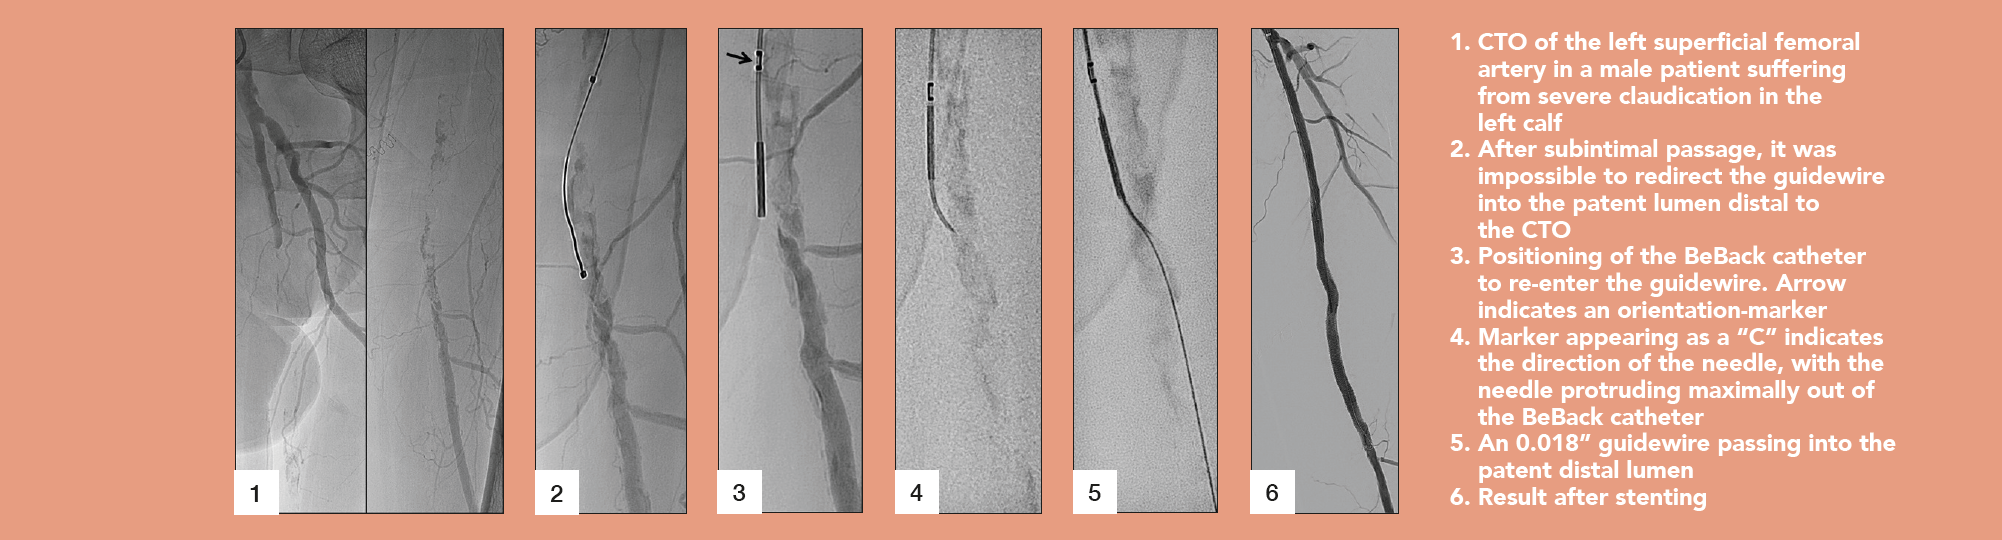

In addition to its main purpose as a crossing catheter for complex, calcified CTOs, the BeBack indeed can be used as a support catheter, since it is quite stable and stiff. This feature is very helpful in difficult total occlusions. It also can be used as a re-entry catheter—for example during a recanalization of a CTO of the femoropopliteal segment. In the typical situation of being stuck subintimally, unable to pass the guidewire back into the true lumen distal to the CTO, the BeBack reliably helps to re-enter the distal patent segment of the artery.

This depends on the type of lesion and the problem encountered during the intervention. For example, a typical femoropopliteal CTO is usually approached from antegrade. In case of inability to penetrate the guidewire into the CTO, either due to dense fibrosis of the proximal cap or severe calcification, the BeBack catheter is used as a crossing device by pushing the adjustable needle just a little bit out of the tip of the 4F catheter. More frequent, however, is the situation that the guidewire passes the CTO subintimally, and reconnection to the patent lumen, distal to the CTO, fails. As mentioned, the BeBack catheter is then used as a re-entry-device by protruding the curved inner needle further out of the tip of the catheter. Different to other re-entry devices is that the BeBack is 4F compatible, instead of 6F, and introduction into calcified, tight lesions may be easier. Yet, it can be used over a 0.018” guidewire, which is often the guidewire of choice in difficult CTOs, improving stability and success compared to 0.014” guidewires.